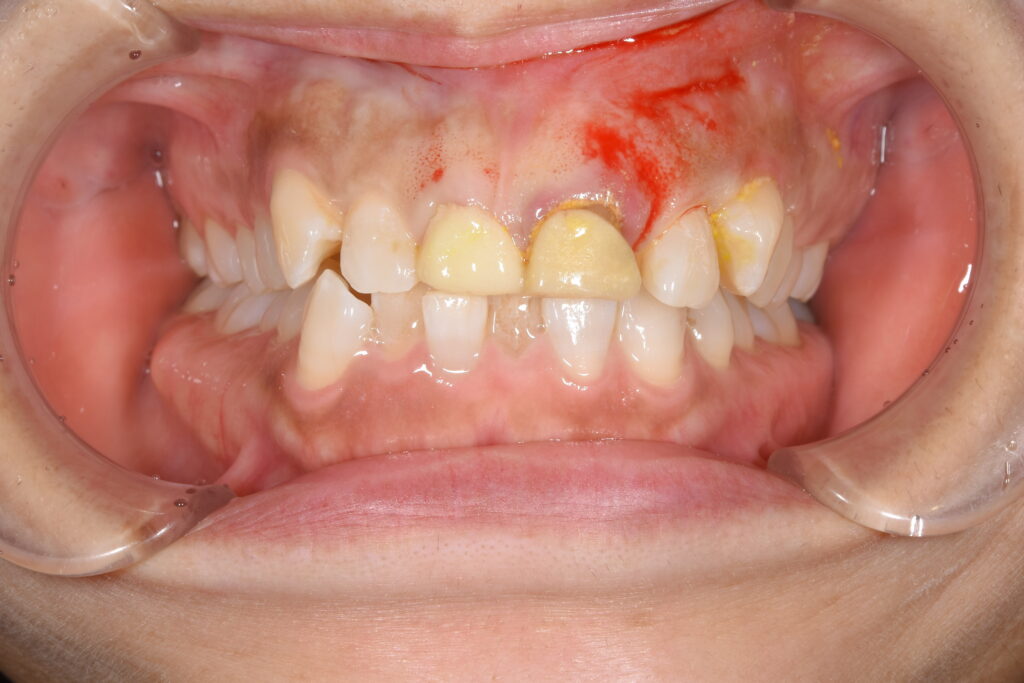

【初診時の状態】

上前歯2本が他院で仮歯を装着して頂いていたが、外れそうとのことで受診されました。検査の結果、虫歯でどうしても残すことが困難な状態でした。相談の上、治療終了時に長持ちする治療を希望され、矯正治療行い、その後前歯にセラミック治療を行うことになりました。以下に治療終了時の状態です。